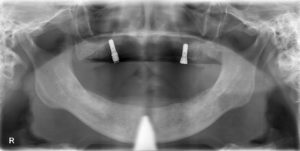

【術前】

【術後】

本日の手術時間は約1時間。

術後CTも撮影し、問題なく手術終了を患者様と確認しました。